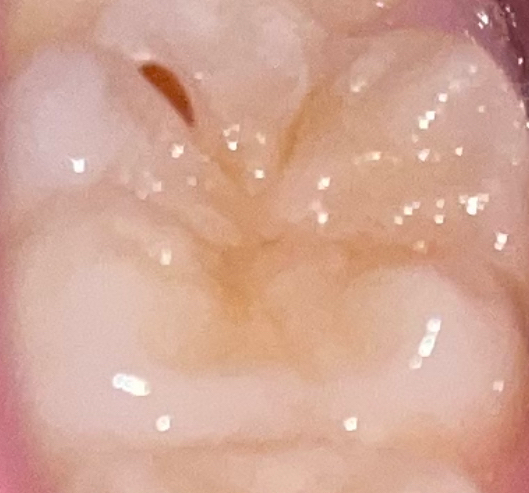

음식물이 아니라 충치가 생긴게 아닌가 생각됩니다. 사진이라 정확하진 않지만, 만약 음식물이라면 치과에 가셔서 제거를 해달라고 하셔야될것같습니다.

아무래도 음식물이 한 곳에 저류하게 되면 충치가 생길 가능성이 큽니다. 따라서 치과를 방문하여 제거하는 것이 필요해보입니다. 이쑤시개나 일반적인 기구를 계속 사용하다 보면 해당 조직을 손상시킬 수 있으므로 몇 번 시도 이후에도 빠지지 않는다면 치과 방문 후 해당 음식물을 제거하는 것이 가장 안전합니다.

치아의 손상이 있어 음식물이 낀것으로 보입니다.

사진의 경우 치아 표면의 깊은 주름에 음식물이 끼인것 처럼 보입니다. 당장 충치로 진행되진 않겠지만 반복적으로 끼이면 결국 충치로 진행될 것이기 때문에 치과에 방문하셔 해당부위는 홈메우기 혹은 레진 충전이 필요할 수 있습니다.